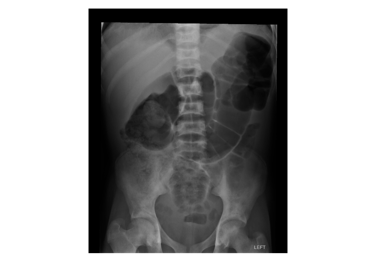

LEARN MOREThis abdominal radiograph is an example of the cases a candidate may be shown in the Final FRCR (Part B) oral examination.

Candidates may be told that the patientpresented with abdominal pain and would be expected to identify the skeletal abnormality which leads to the diagnosis of sickle cell anaemia. Candidates may then be asked to discuss the possible causes of abdominal pain in a patient with this

underlying diagnosis. Candidates will not be required to window, zoom or otherwise manipulate this particular image in order to make a diagnosis.